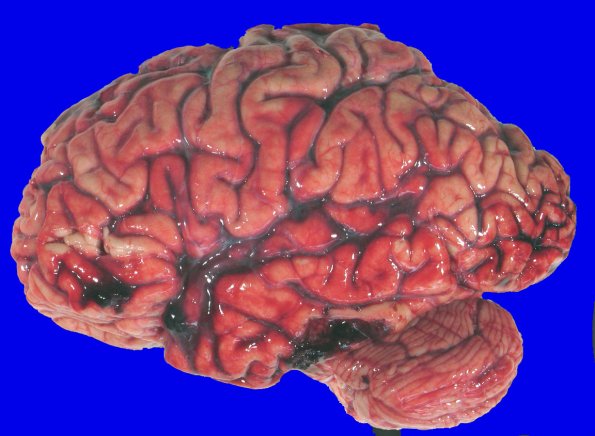

Subarachnoid hemorrhage of the left temporal, parietal, and occipital lobes and cerebellar hemispheres. An organizing blood clot (3 x 2 x 2 cm) was present in the subarachnoid space with an extension into necrotic regions of the middle and inferior temporal gyri and an area of discoloration and necrosis (1 cm diameter) in the left occipitotemporal gyrus.